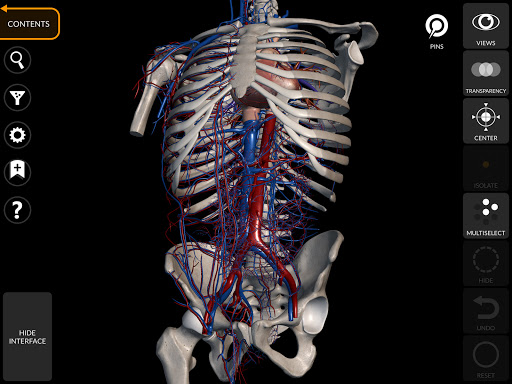

Thông qua giao diện đơn giản và trực quan, bạn có thể quan sát mọi cấu trúc giải phẫu từ mọi góc độ.

Các mô hình giải phẫu 3D đặc biệt chi tiết và có kết cấu lên đến độ phân giải 4k.

• Hệ thống tim mạch

• Xoay và phóng to từng mô hình trong không gian 3D

• Tùy chọn ẩn hoặc cô lập một hoặc nhiều mô hình đã chọn

• Bộ lọc để ẩn hoặc hiển thị từng hệ thống

• Chức năng trong suốt